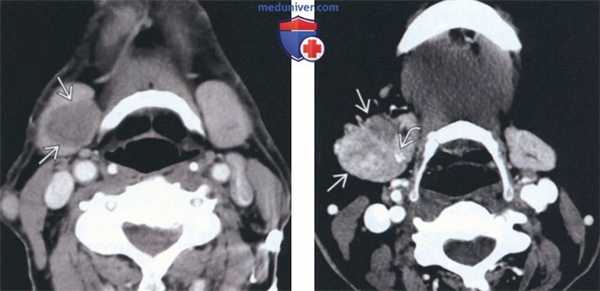

(Слева) На аксиальной КТ с КУ определяется очаговое гиподенсное образование. обусловливающее увеличение правой под нижнечелюстной железы (ПНЖ). Образование хорошо отграничено, что является признаком доброкачественности, но, тем не менее, требует патоморфологического подтверждения.

(Справа) На аксиальной КТ с КУ у другого пациента определяется неравномерное диффузное увеличение правой ПНЖ. Очаговое обызвествление с внутренней стороны позволяет заподозрить ДСО. Томография не позволяет различить злокачественную и доброкачественную опухоль за исключением случаев с явными признаками инвазии или лимфаденопатии. (Слева) На аксиальной МРТ (Т2 ВИ) у молодой женщины с пальпируемым образованием в поднижнечелюстной области в левой ПНЖ визуализируется хорошо отграниченная опухоль овальной формы с гиперинтенсивным сигналом. Признаки распространения опухоли за пределы ПНЖ отсутствуют.

(Справа) На аксиальной КТ с КУ у другого пациента определяется неравномерное диффузное увеличение правой ПНЖ. Очаговое обызвествление с внутренней стороны позволяет заподозрить ДСО. Томография не позволяет различить злокачественную и доброкачественную опухоль за исключением случаев с явными признаками инвазии или лимфаденопатии.